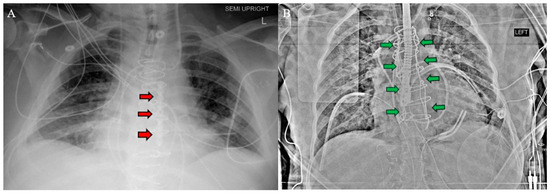

After establishing cardiopulmonary bypass through the inferior partial sternotomy, the two-stage sternotomy was then completed with the separation of the superior sternum with the oscillating saw. Direct SVC cannulation was established, and the remainder of the heart and great vessels were dissected. Severe, densely calcified adhesions were encountered between the aorta and the pulmonary artery, which required extensive dissection. Following this complex dissection, cardiectomy and transplant were performed routinely. After transplantation, the chest was left open and packed for hemostasis, and the patient was returned to the OR on POD 1 for sternotomy closure. One longitudinal sternal plate was used with sternal wires posterior to the plate to close the sternum (Figure 3A).

Prior to OLT on POD1, the CVP was mildly elevated, so continuous renal replacement therapy was initiated to remove fluid. The CVP came down appropriately, and OLT was performed without complication. The chest and abdomen were both simultaneously closed after liver transplantation, with a Robiscek technique utilized for sternal closure (Figure 3B). The patient recovered in the CTICU until POD17 as she required a prolonged course of dobutamine inotropic support, which was anticipated. The postoperative evaluation revealed a significant improvement in LVEF, tricuspid regurgitation, and cardiac output with no evidence of rejection on EMB. The patient remained in the CTICU until transfer to the general transplant medicine floor on POD17 and was discharged on POD58. As of three months post-transplant, the patient remained clinically stable with excellent graft function and no evidence of rejection.

Figure 3. Postoperative chest X-ray for (A) Patient 1 and (B) Patient 2 demonstrate sternal plate used in Patient 1 (red arrows A) and Robicsek technique used in Patient 2 (green arrows B).